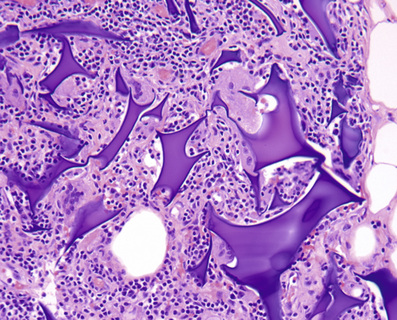

• Salt-split skin studies (DIF/IIF): leads to a separation of the skin at the DEJ, and allows you to see where the immunoreactants are depositing; allows for distinction between various subepidermal blistering diseases (Table 7-10, Fig. 7-12)